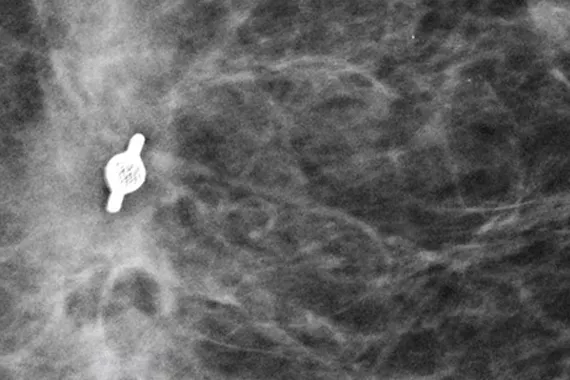

Marcadores de biopsia Tumark®

Com um design inteligente para permitir a visibilidade a longo prazo. Todos os marcadores Tumark são não bioabsorvíveis, biocompatíveis e permanentes, proporcionando uma excelente visibilidade, sendo concebidos para se moverem o mínimo possível.1

As pesquisas indicam que os marcadores de biopsia Tumark Professional X, Q e Vision são precisos e fáceis de utilizar.1

afirmam que a visibilidade por ultrassom foi boa a excelente após a colocação1

dos marcadores foram colocados com precisão na área prevista1

concordaram que o dispositivo é fácil de utilizar1